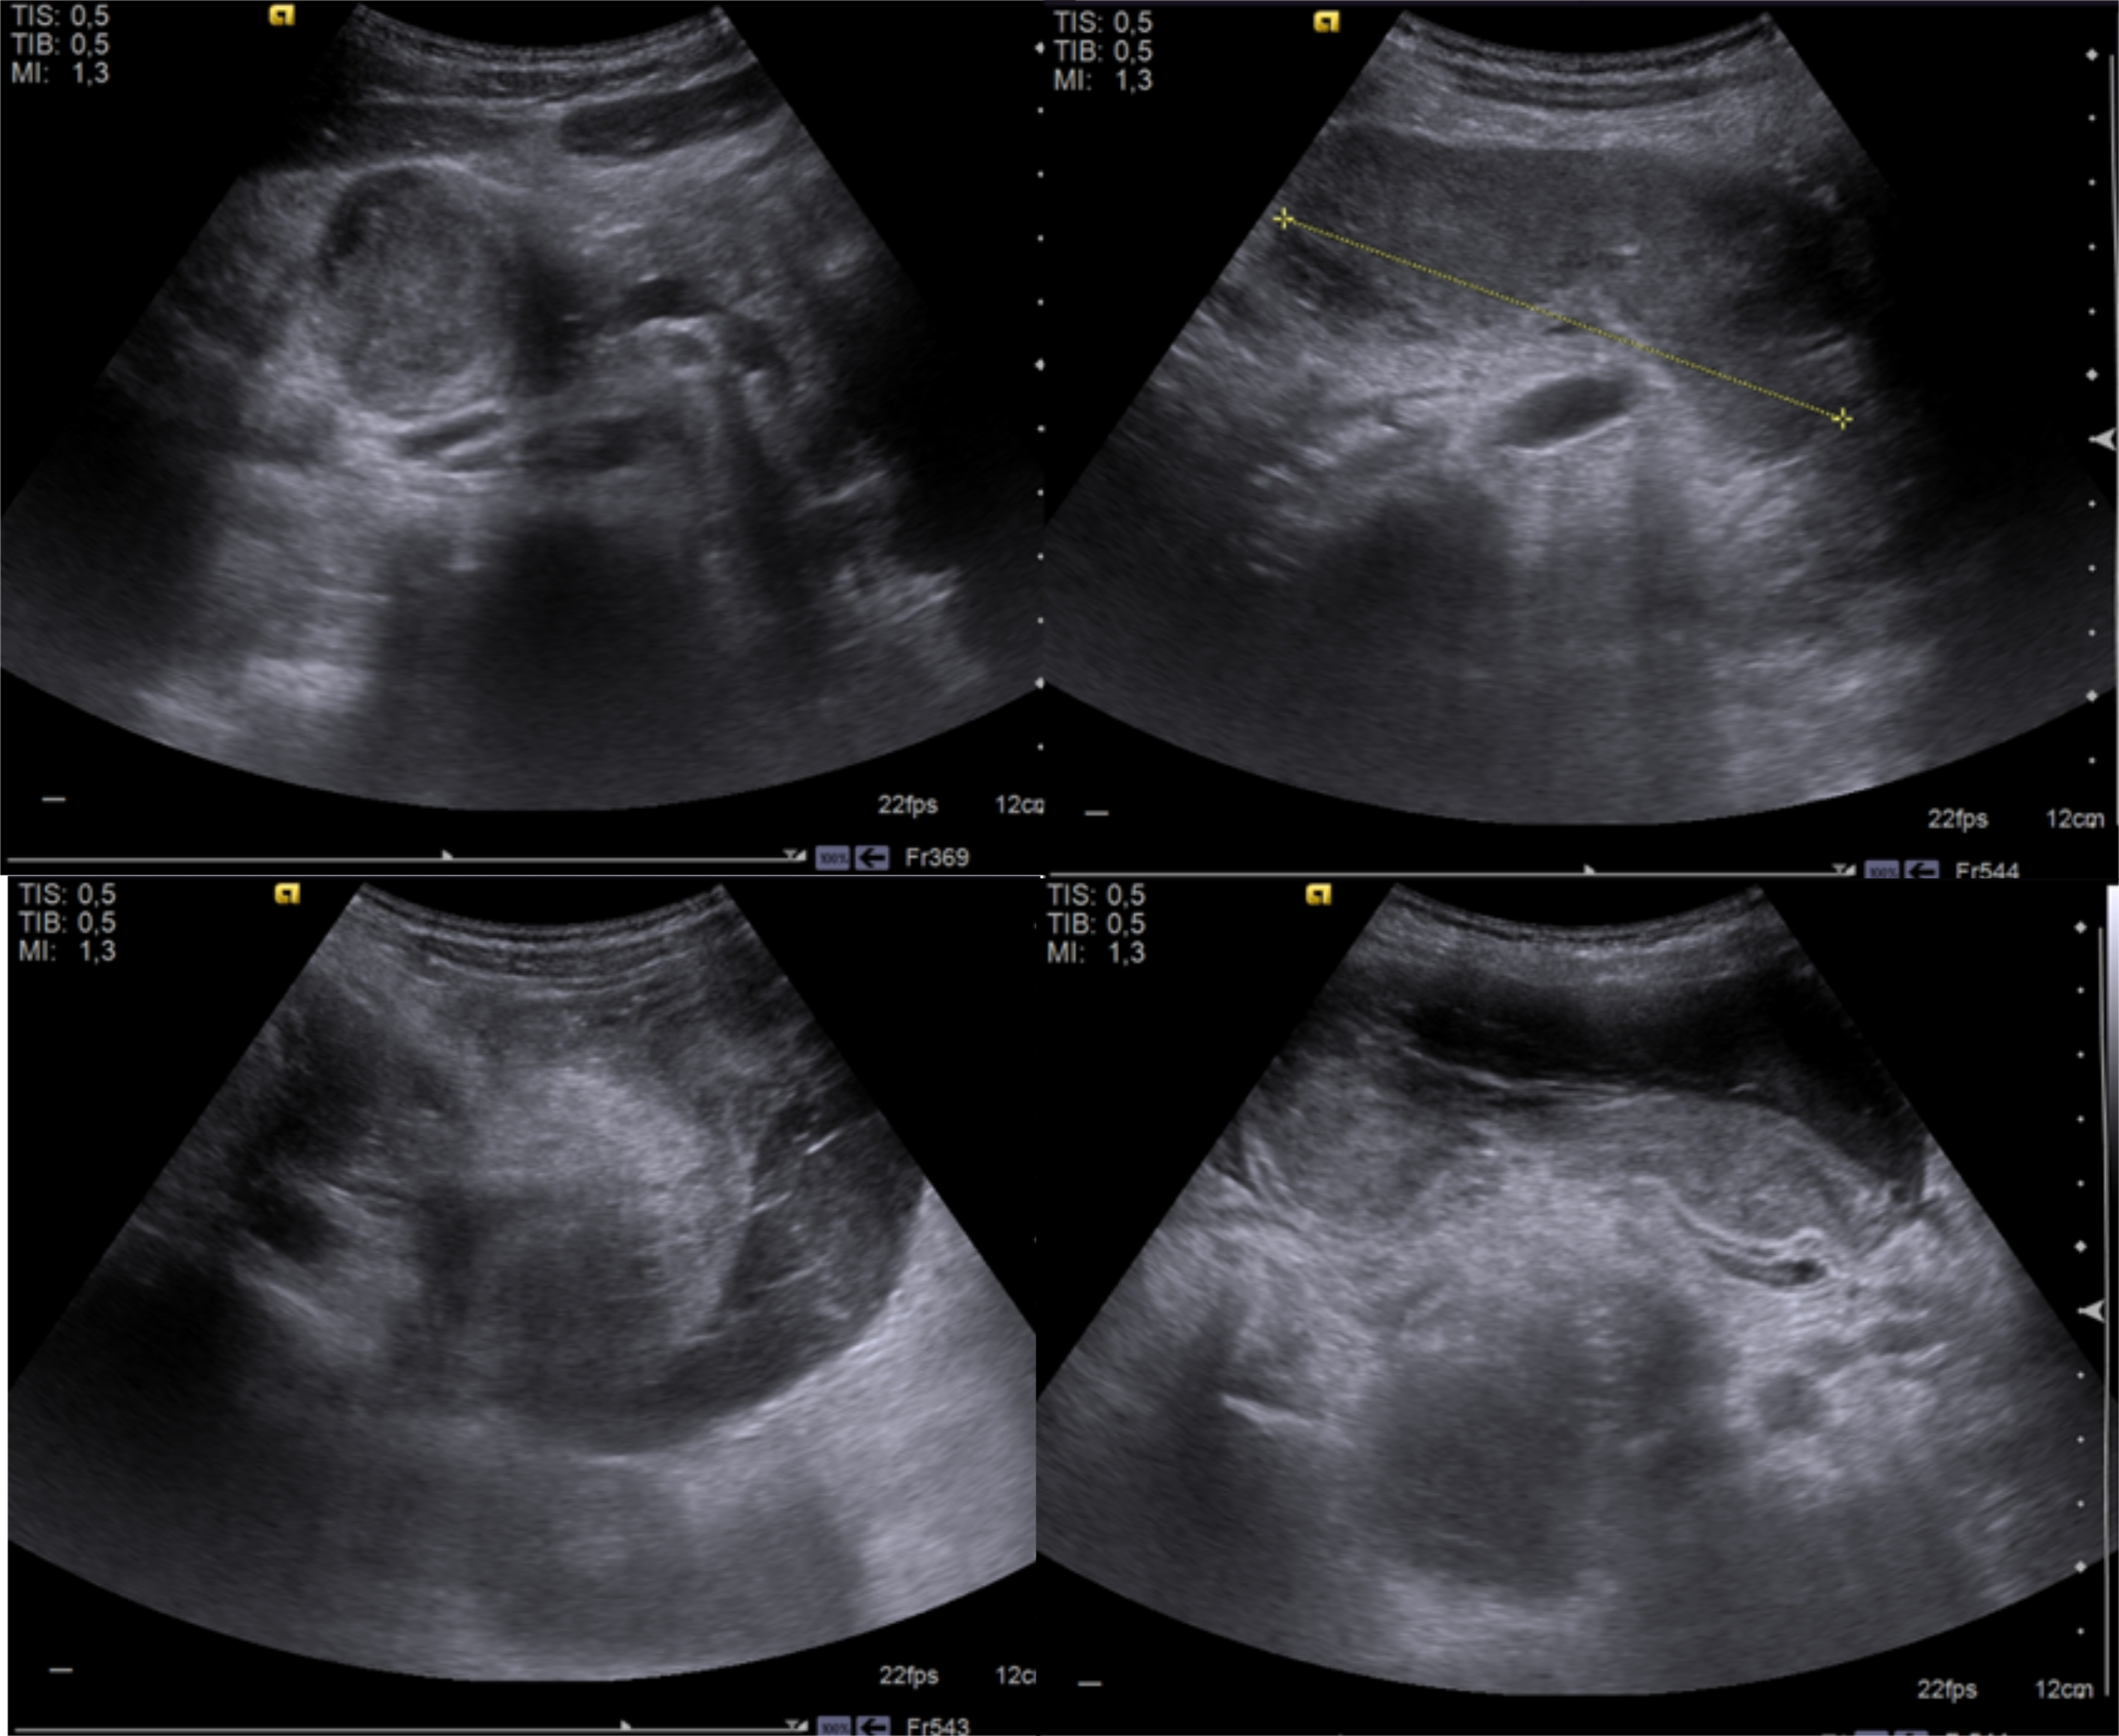

Duodenal hematoma is a rare complication of endoscopic duodenal biopsy, with just a few cases reported in children in the literature available.

The authors present a case of a 13 year-old girl, with a history of Noonan Syndrome and neurofibromatosis type 1, who presented abdominal pain and vomiting after an endoscopic duodenal biopsy.

In this article, we describe the clinical case, imaging findings, evolution and therapeutic approach.